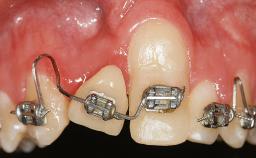

Implant Placement in the Esthetic Zone and Coverage of Multiple Gingival Recessions

This case illustrates use of a modified ‘tunnel’ technique, which has been shown to be highly effective in root coverage procedures. The tunnel technique is used to achieve soft-tissue augmentation across the anterior area, including the planned implant site, using collagen matrix as grafting material. The patient is a 47-year-old woman with high esthetic expectations. Her main concern was the appearance of the anterior teeth and their “elongation”.